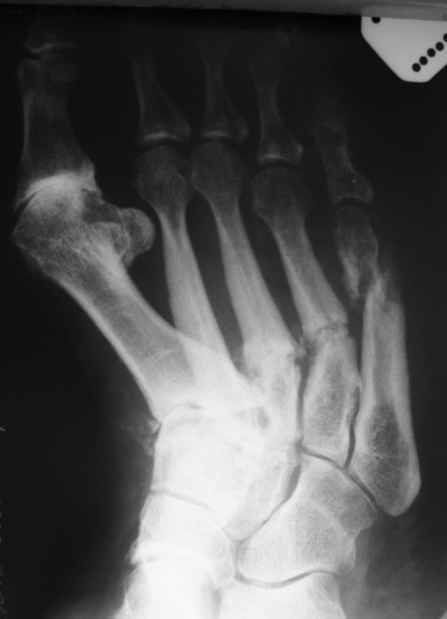

Уважаемые коллеги. Помогите определиться с дальнейшим лечением данного клинического случая (Ро - граммы прилагаю ).

Из анамнеза: Со слов больной травмы отрицает. Считает себя больной последние 5 лет, когда в первые появились боли в стопах и правом тазобедренном суставе. Обращалась в РТП по месту жительства, выполнялись Ро - граммы ( на руках ), без патологии. болевой синдром постепенно наростал. Пациентка лечилась консервативно по месту жительства с переменным успехом. Выполнялись этапные Ро - контроли ( к сожалению Ро - утерян в РТП ). Со слов пациентки Ро - картина ухудшалась. Данное ухудшение с февраля 2009 года. больная стала отмечать отрицательную динамику, появилось искривление области плюсны по тыльной поверхности стопы, крепитация отломков, усиление болевого синдрома, отёк в области правой стопы, формирование экзостоза головки 1 плюсневой кости, уплощения продольного свода стопы, невозможность носить ежедневной обуви ( в плоть до домашних тапочек ). и вот она измученная лечением обратилась к нам...Трудовой анамнез не отягощён. Работает поваром в столовой.Местно: У больной имеется отёк мягких тканей тыла стопы. при осмотре продольный и поперечный своды стопы уплощены. имеется вальгусная деформация 1 го пальца правой стопы. Экзостоз головки 1 плюсневой кости. Кожа над поверхностью не изменена. признаков гипертермии и гиперемии нет. При пальпации отмечается болезненность в проекции диафизов 2-4плюсневых костей по тыльной поверхности. Так же отмечается крепитация отломнов в проекции 5 плюсневой кости. Признаков сосудистых и неврологических расстройств нет. При стоянии на обеих ногах, отмечается болезненность в проекции 5 плюсневой кости правой стопы.

Действительно, не имея полного описания пациентки (вес, возраст, и прочие мелочи) о причине данных переломов можно строить различные догадки. Возможно, при детальном выяснении анамнеза, всплывёт какая-то незначительная травма (оступилась, неправильно поставила ногу), которая не акцентировала на себе внимание, но с учётом сопутствующих факторов, о которых многие говорят выше, произошла такая картина. Кстати как у пациентки с остеопорозом. По рентгенограмме признаки имеются, а проблемы в I плюстне-фаланговом суставе появились, как мне кажеться значительно раньше переломов (артроз практически III-IV стадии). Если будете проводить даообследование, интересно было-бы узнать конечный результат. Всем удачного месяца.

Как правильно заметил Михаил Васильев, нехватает некоторых мелочей. Пациентка В., возраст 45 лет. Вес 64,5 кг. Рост 168 см.

Мы так же как и доктор Кулешов установили диагноз стресс перелома или болезнь Дойчлендера. Пациента сейчас находится в гипсовой иммобилизации сроком уже 3 недели. До обращения к нам, пациентка лечилась по месту жительства без какой либо фиксации, нагружая ногу полностью.

Высылаю ещё Ро - граммы. Мне кажется должно получиться.

Кликните для загрузки файла IMG_5249.JPG

36KB (36989 bytes)

Алексей 04 Декабрь 2009, 23:54

ещё фото боковая проекция правой стопы

Ро - левой стопы. последние 3 недели присоеделись боли. Если позволите Ро - находка!!!

Патологические переломы на обеих стопах...

И не большой вес у пациентки...

Явно какая то общая причина.

Нужно дифференцировать с mts, tbz,проблемами паращитовидных желез.Определите уровень кальция в крови.